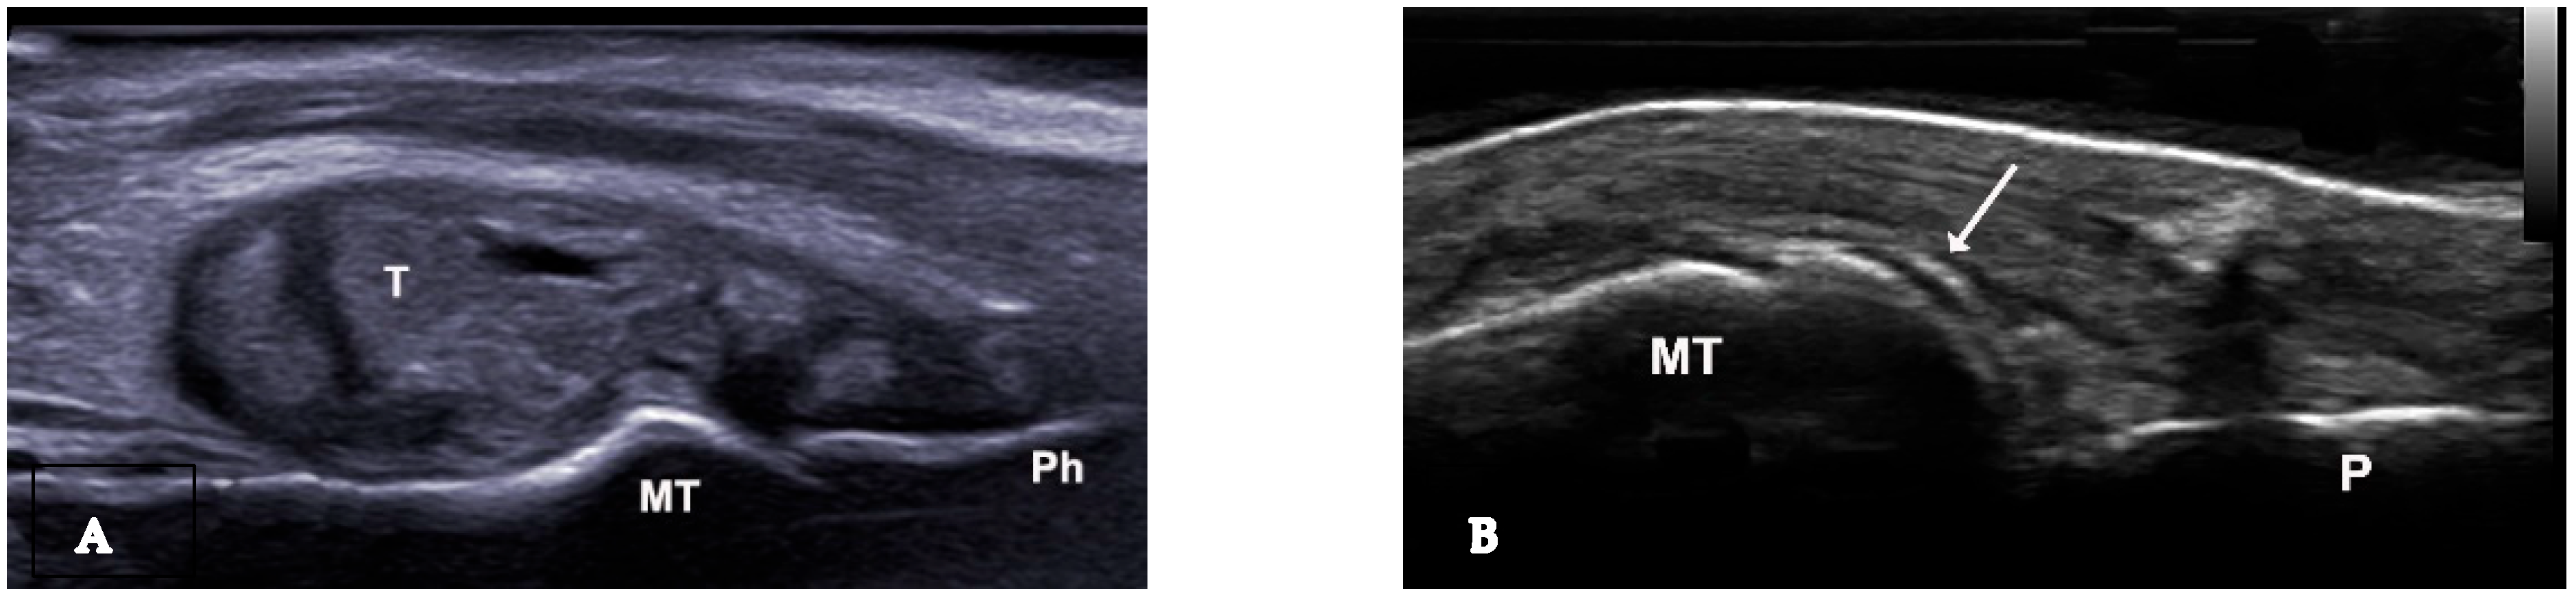

The double contour sign (DCS) indicates deposits of MSU crystals on cartilage surfaces, distinguishable from calcium pyrophosphate crystal deposits typically found within cartilage, highly specific for gout (Figure 2B and Figure 6A,B). Due to MSU crystal deposition, the reflectivity of the chondrosynovial interface is no longer angle-dependent, allowing for easy panoramic visualization of the entire chondrosynovial interface [18,19]. Like the tophus, the DCS should be sought in symptomatic joints, including the first metatarsophalangeal joints (dorsal and palmar planes) and the trochlear cartilage of the knees (suprapatellar plane in maximum flexion). The DCS may be less visible in thin cartilage (tarsal joints) or damaged cartilage, such as in osteoarthritis. Additionally, certain ultrasound features can be mistaken for a DCS, leading to false positives due to several factors: first, the normal hyperechoic appearance of the synovium, where the hyperechoic band appears regular, like a line drawn with a pen. A “true” DCS adheres to the cartilage during dynamic movements. Second, the presence of joint effusion enhances the echo of the posterior wall (increased ultrasound propagation) and may accentuate the normal hyperechoic appearance of the synovium. Finally, thin cartilage (small joints and/or associated osteoarthritis) with chondrocalcinosis and calcium deposits often localized in the intermediate layer of the cartilage [14,16]. Regarding the diagnostic performance of the DCS sign, a recent study by Cipolletta et al. emphasized that dynamic examination significantly improves the effectiveness of US in differentiating between gout and calcium pyrophosphate dihydrate CPPD crystal arthritis. Their results indicated that, with dynamic examination, the DCS sign moved with the cartilage in all cases of gout, whereas it moved in the opposite direction in CPPD patients. [20]. In 2022, Filippou et al. conducted an anatomical cadaver study to compare US DCS findings with pathological features, aiming to evaluate how crystal location affects ultrasound characteristics. The study was performed on upper limb joints until calcium pyrophosphate (CCP) deposits were detected according to OMERACT criteria. The affected joints were then examined pathologically, with crystal deposition described. The findings concluded that monosodium urate (MSU) crystals in gout are located directly on the chondral surface and cause the DCS sign to move with the cartilage. In contrast, CCP crystals are found in capsules and/or ligaments, above the hyaline cartilage, and do not exhibit dynamic sliding during US examination [21].

Figure 6.

Ultrasound features of “double contour sign” visible on the cartilage surface of the femur (A) and first metatarsal bone (B).